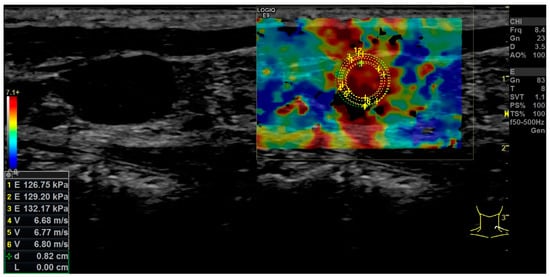

| Strain Elastography | Qualitative report of stiffness (soft or hard) | Q-analysis of strain elastography with Q-ratio; two ROI in the center, four at the margin of the LN and two in the surrounding soft tissue. The ROIs within the LN included areas with the lowest and the highest stiffness. The diameter of each ROI was 2–3 mm. |

| Shear Wave Elastography | Single ROI drawn with the largest possible diameter not extending beyond the LN margins (kPa). | Repeated (3x) measurement by kPa and m/s using ROI drawn with the largest possible diameter not extending beyond the LN margins. The values of the repeated measures were used to build a mean value for overall LN stiffness in kPa and m/s. |